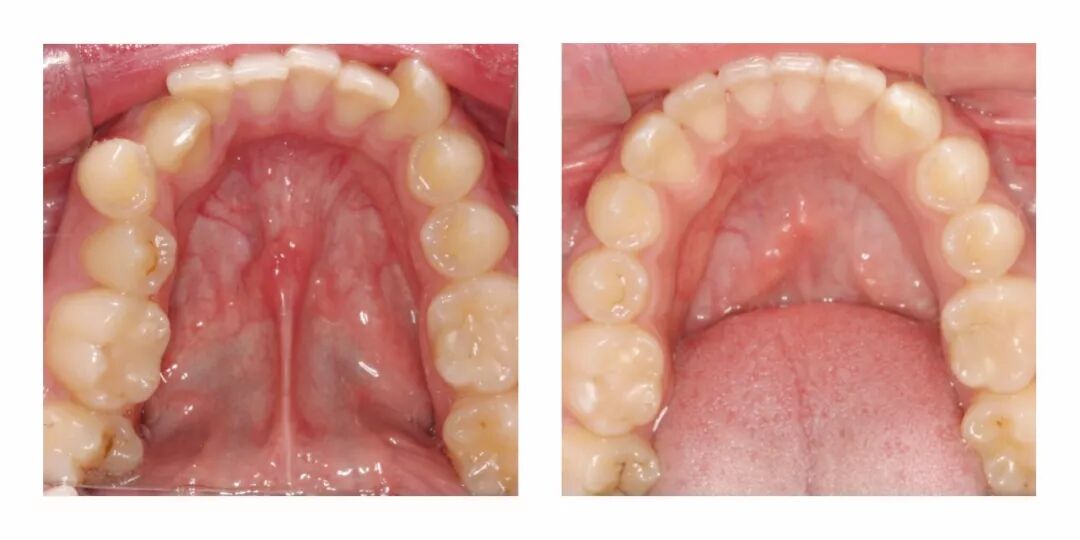

他家有一些具体的正畸案例,效果也很惊人。▼

感觉虽然只是矫正了牙齿,但是整体颜的感觉都不一样了有木有?

从苹果肌到鼻子的形状、下巴的线条,都完全变了啊……▼